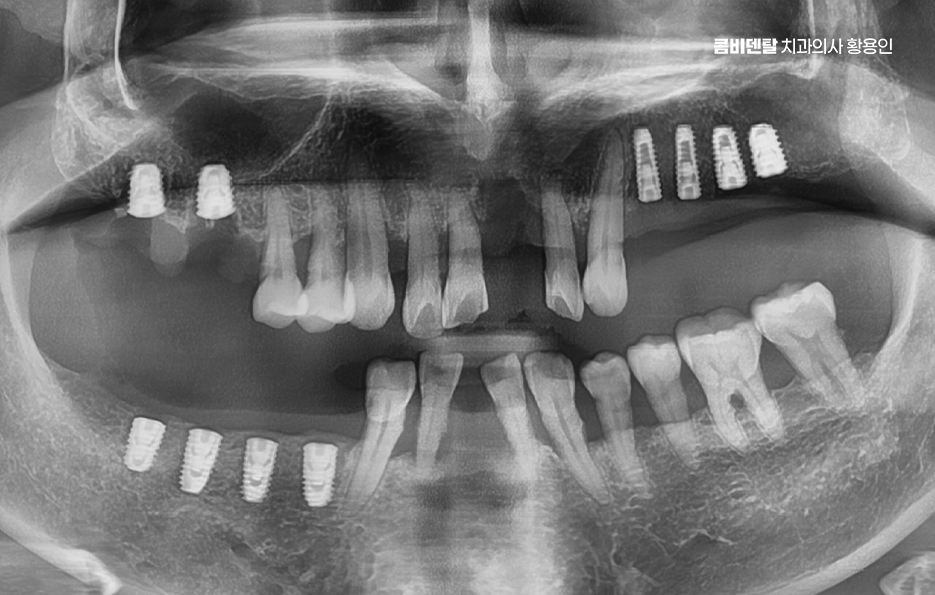

그렇다면 뼈이식을 언제, 어떻게 계획해야 하는지가 중요한데 첫 번째는 임플란트 식립 전 단계에서 충분한 영상 진단과 분석을 통해 뼈의 양과 질을 정밀하게 평가해야 하며 단순 파노라마 X-ray만으로는 확인이 어려운 입체적인 골량이나 신경과의 거리, 부비동 위치 등을 정확히 파악하려면 3D CT 촬영이 필수적이고 이를 통해 상악동 거상술이 필요한지 등을 판단할 수 있어요.

두 번째는 뼈이식을 단독으로 먼저 시행할 것인지, 임플란트 식립과 동시에 병행할 것인지를 결정해야 하는데 뼈 소실 정도가 심하지 않은 경우라면 동시에 진행할 수도 있지만, 뼈가 너무 얇거나 신경과 가까운 부위라면 3~6개월 정도의 치유기간을 두고 뼈이식만 먼저 시행한 뒤, 뼈가 자리 잡은 후에 임플란트를 식립하는 2단계 방식이 안전한 선택이 되는 거예요.

임플란트 뼈이식 안하면 대해서 결론적으로 말씀드리면, 잇몸뼈 상태가 좋지 않은데도 무리하게 임플란트를 진행하거나 뼈이식을 생략하게 되면 결국 치료 실패의 가능성이 높아지고, 수개월 또는 수년 후에 재수술이 불가피해지거나 더 큰 비용과 시간이 소요될 수 있는 상황으로 이어질 수 있으므로 단지 뼈이식은 무섭거나 부정적으로 느끼기 보다는 임플란트의 치료 원리 뿐 아니라 나아가 장기적으로 오랫동안 유지하며 사용해야 하는 자연치아의 대체 치료라는 점에서도 멀리 바라보고 치료에 임하시길 바라고 있어요